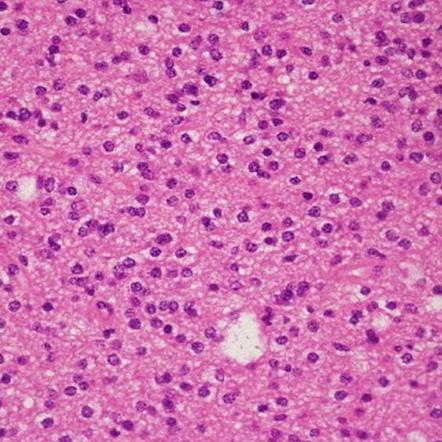

Микрофотографии гистологии глиобластомы головного мозга